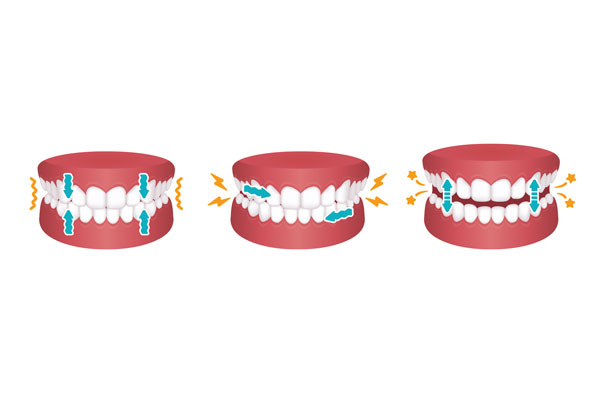

3 différents types de bruxisme

3 différents types de bruxisme